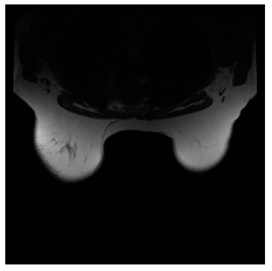

- Prostate-MRI Database (available at: https://wiki.cancerimagingarchive.net/display/Public/PROSTATE-MRI (accessed on 4 November 2021))

Prostate-MRI database contains MRI-type medical images and collects prostate medical images. Some samples are shown in Figure 12e.

Figure 12.

Sampled images in the tested benchmark databases: (a) Breast-MRI-NACT-Pilot (breast), (b) ACRIN-DSC-MR-Brain (brain), (c) NIH (chest), (d) Lung-PET-CT-Dx (lung), (e) Prostate-MRI (prostate), and (f) Other grayscale standard images.